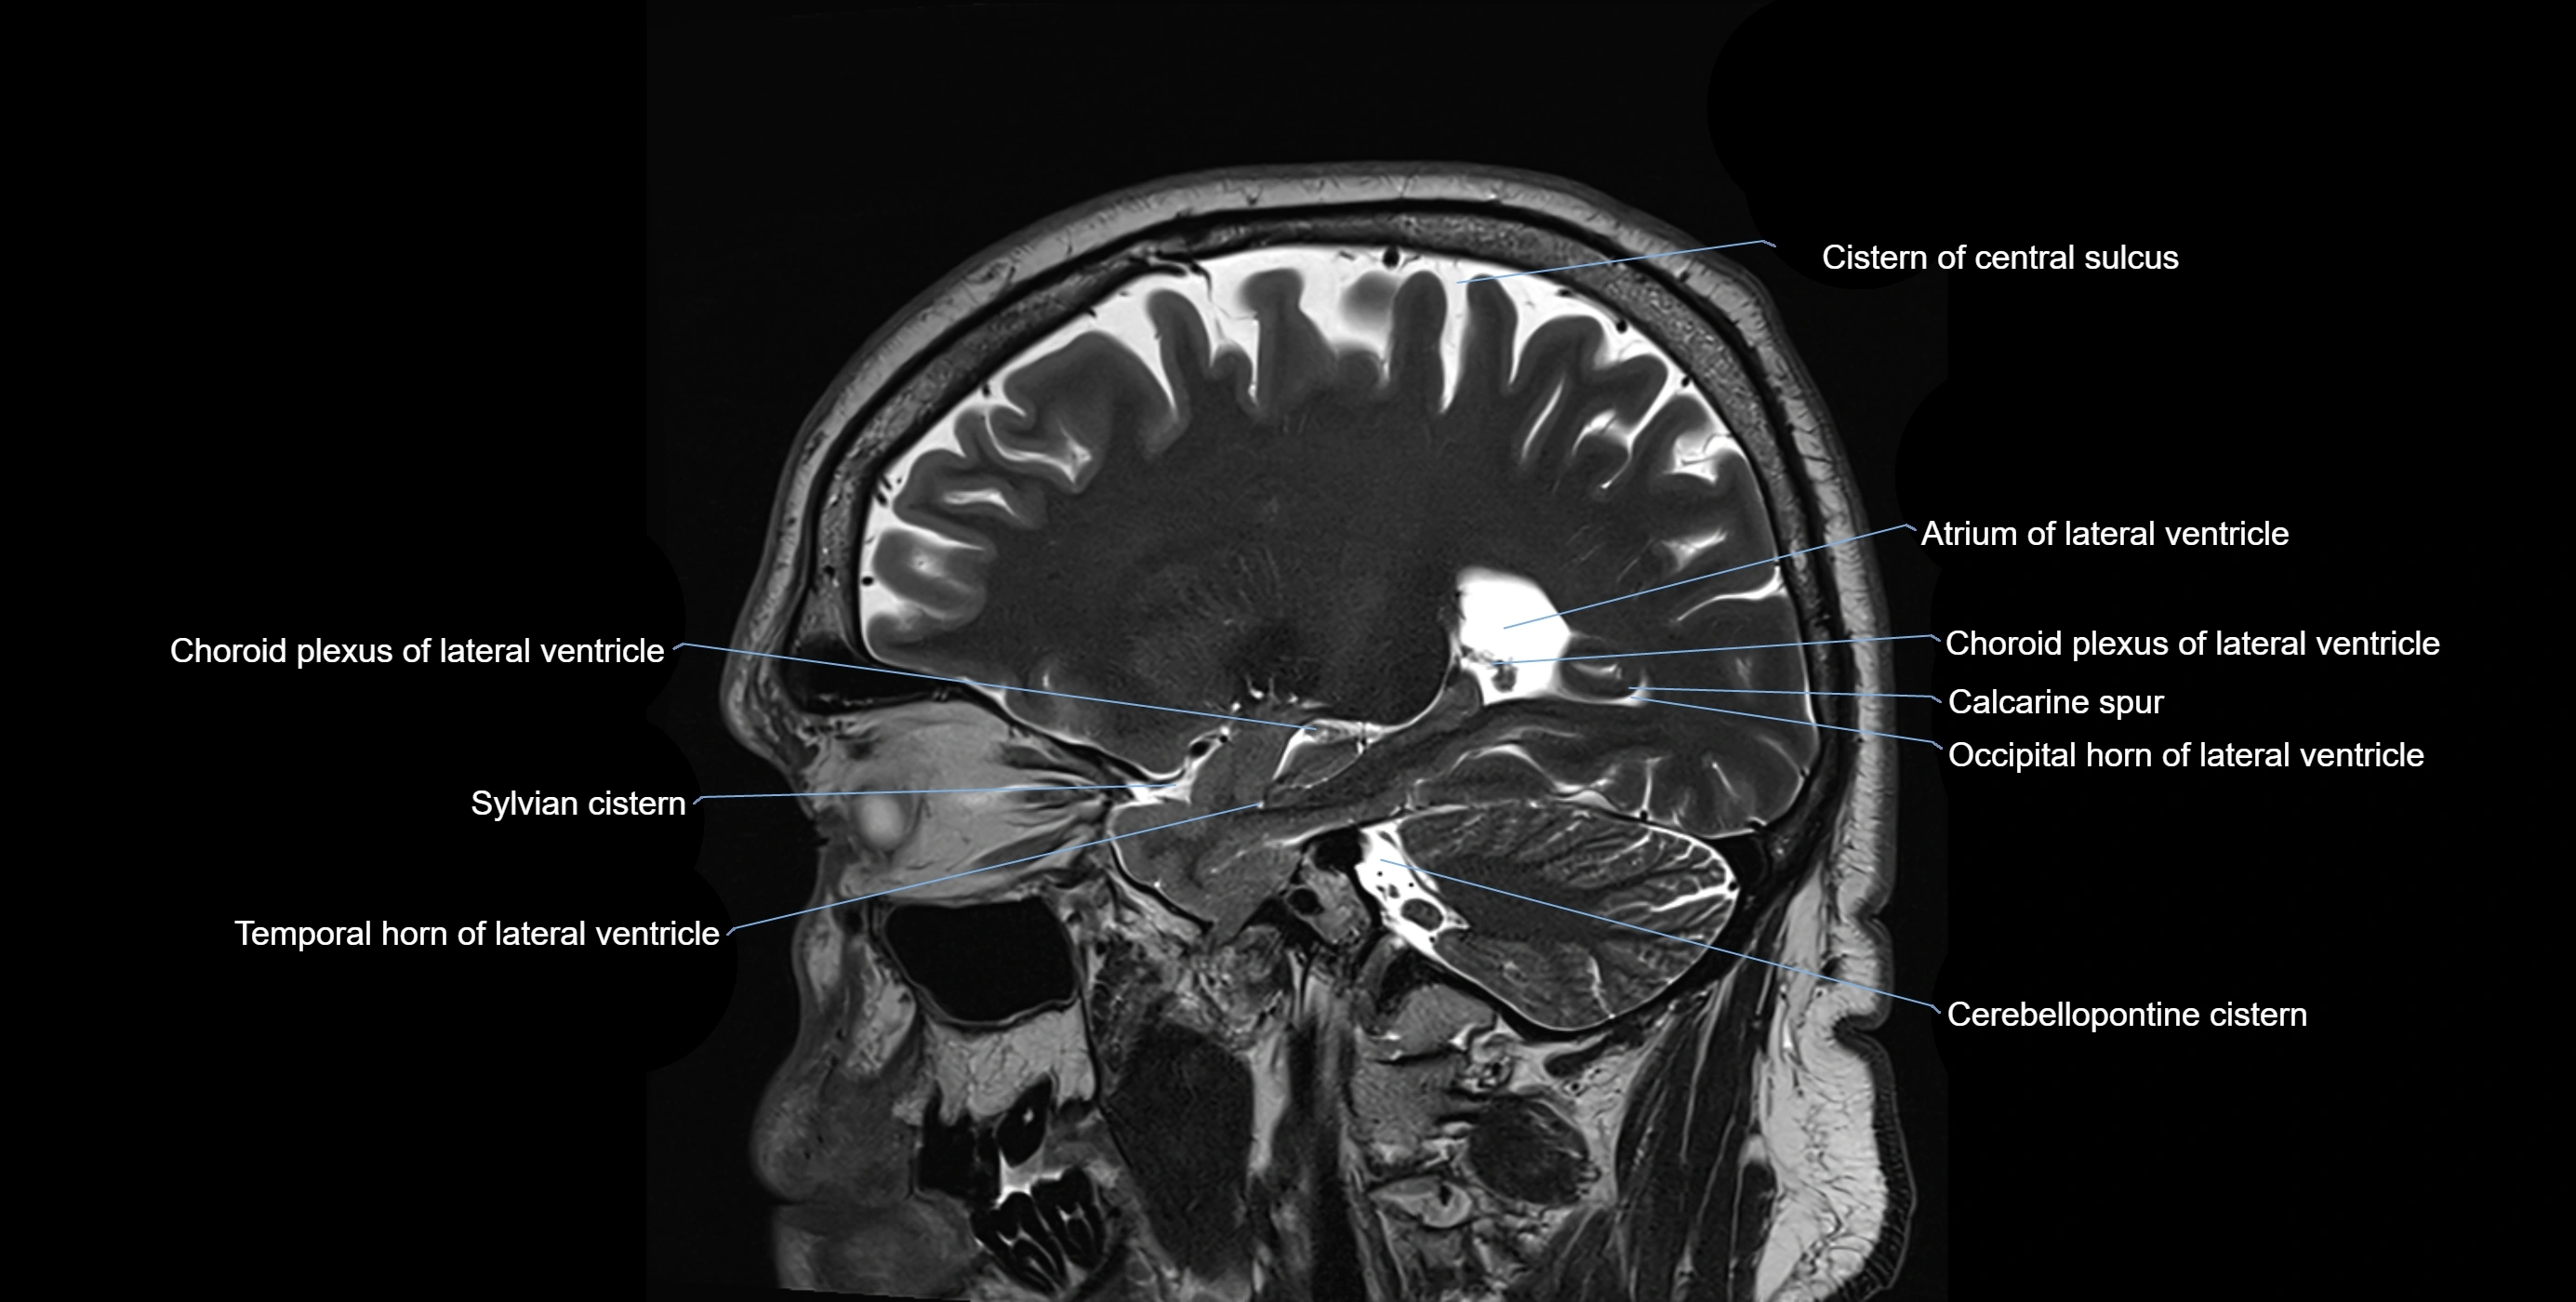

MRI images

image